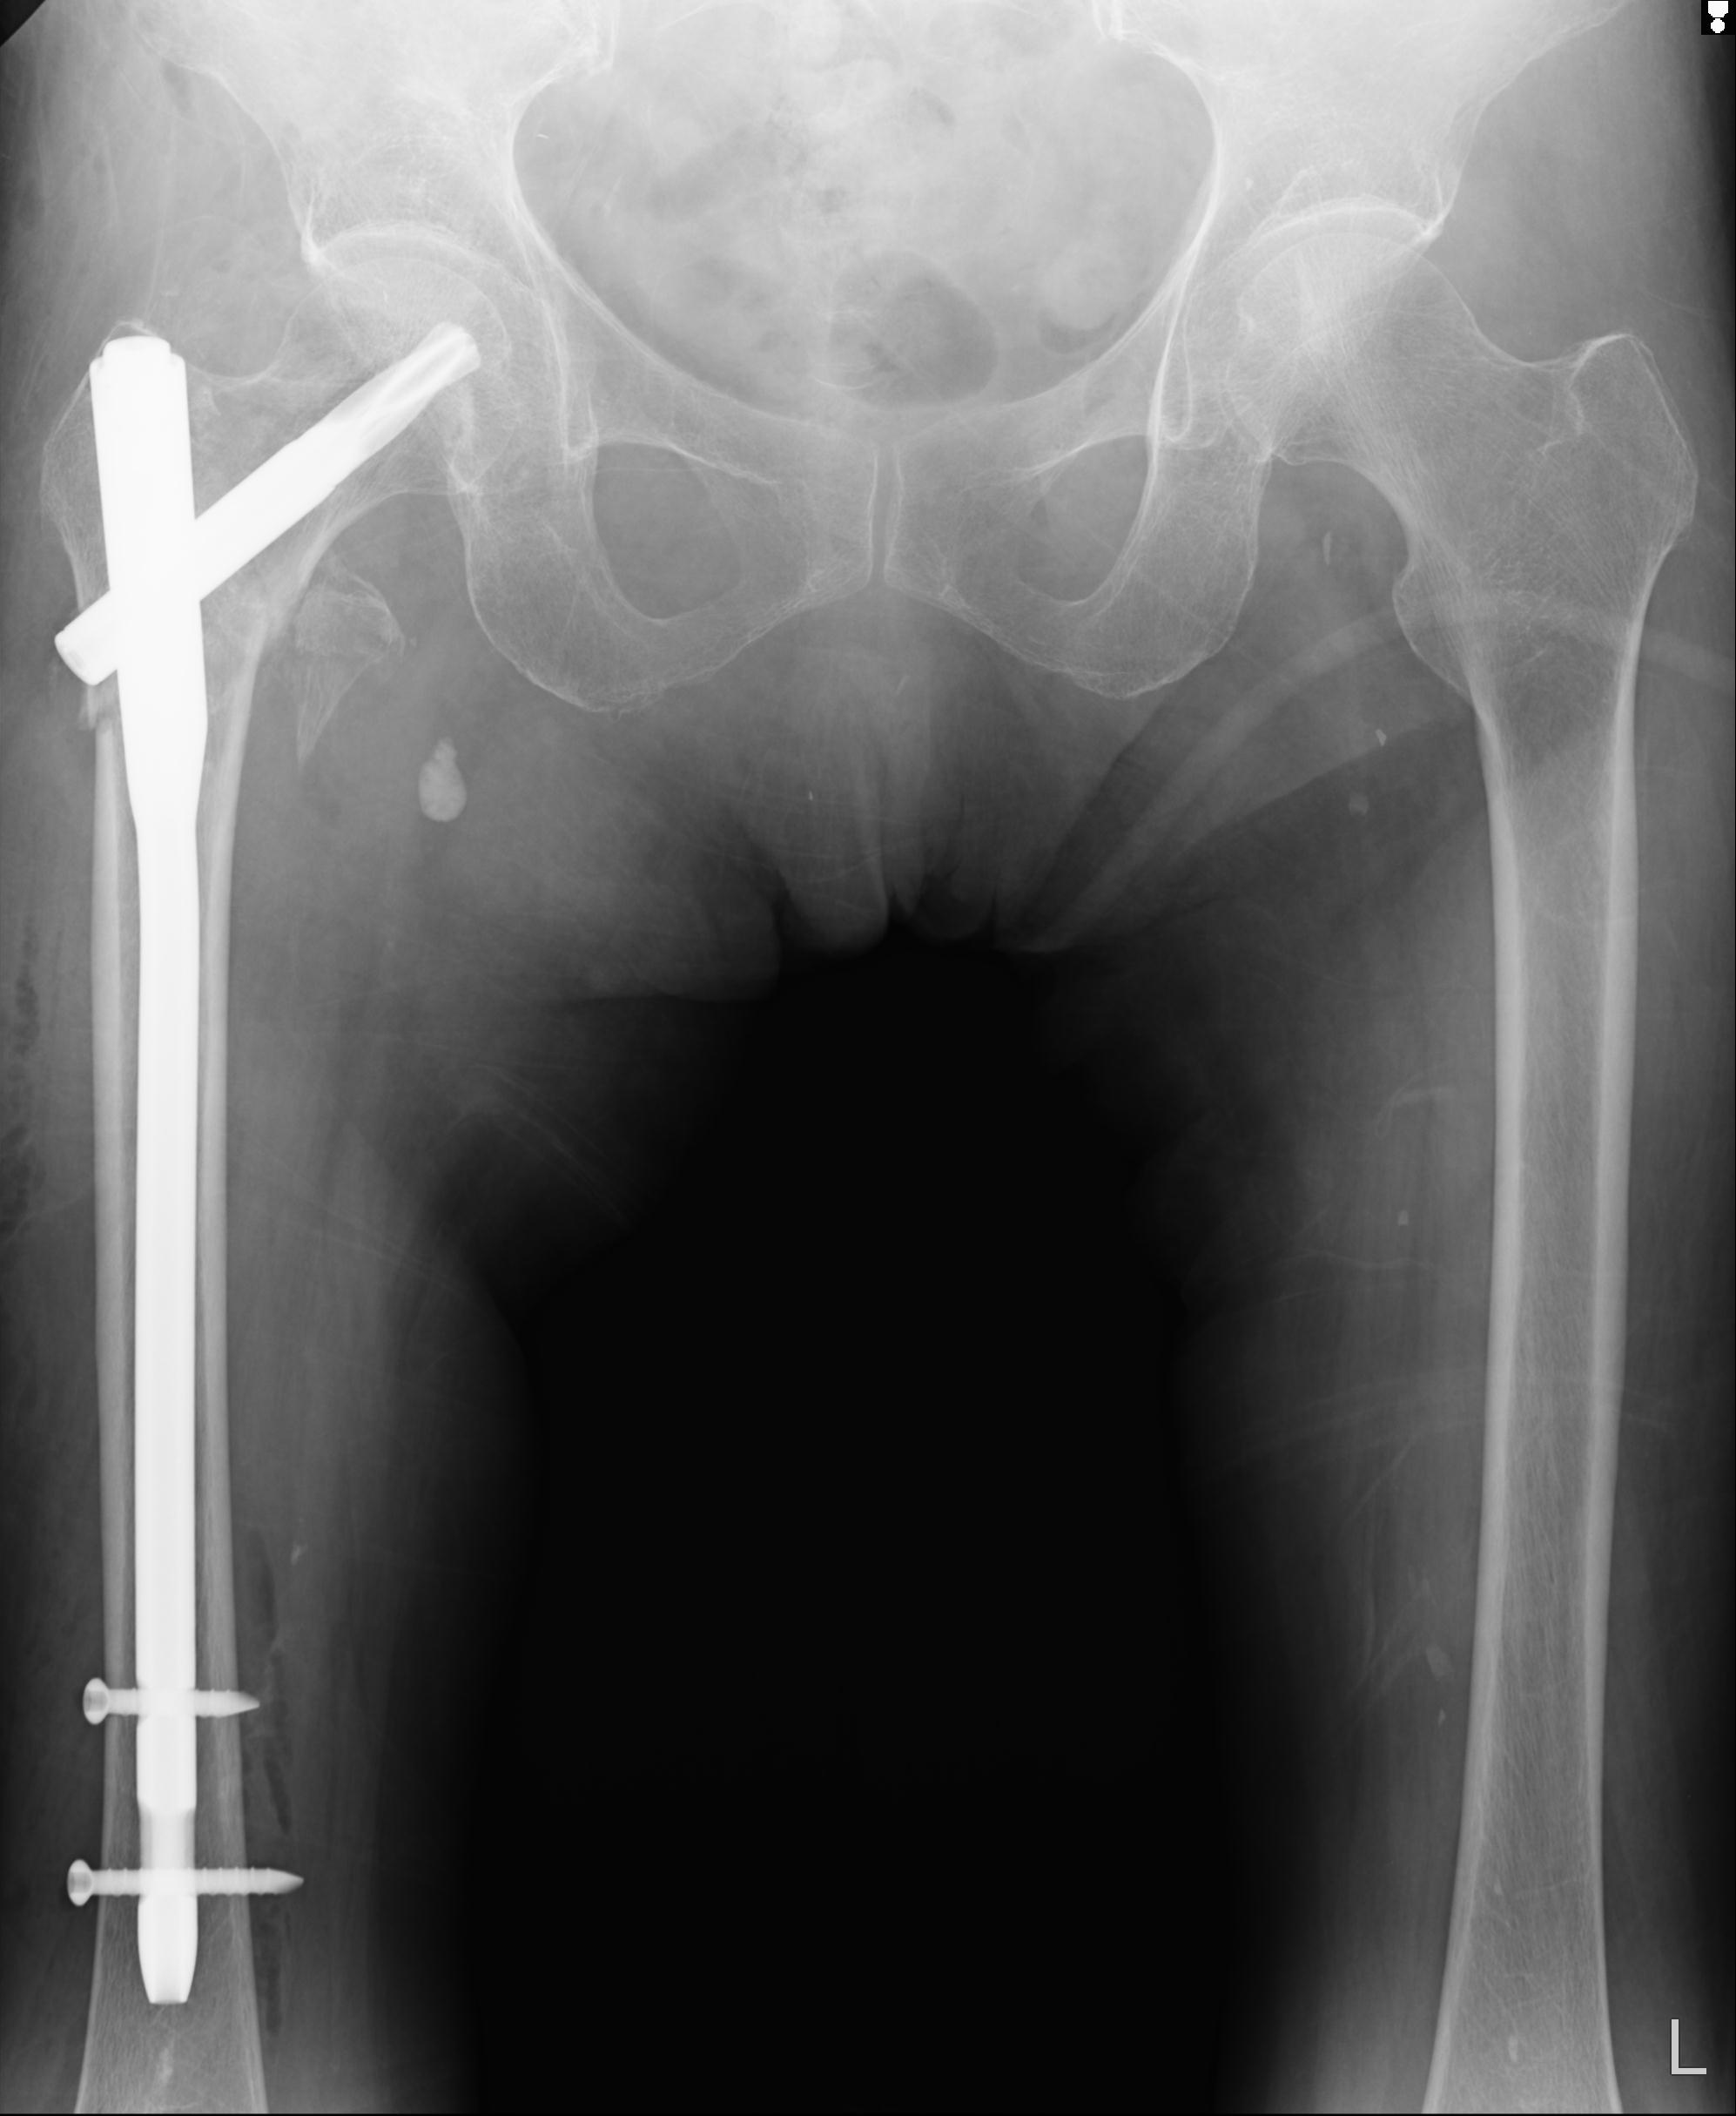

37 1/18 両股正面+軸 1/22 2R 86歳女性 右転子下